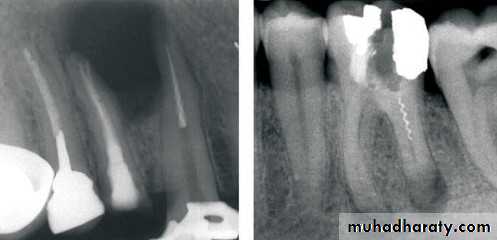

False contraindication of endodontic therapy:- Presence of broken instrument

False contraindication of endodontic therapy:- presence of calcification

- Anatomical difficulties

- Difficulty of retreatment:

Presence of silver cone within the canal.Presence of ceramic crown covering the crown

(to overcome these problems surgical intervension is indicated or removal of the old root canal filling)